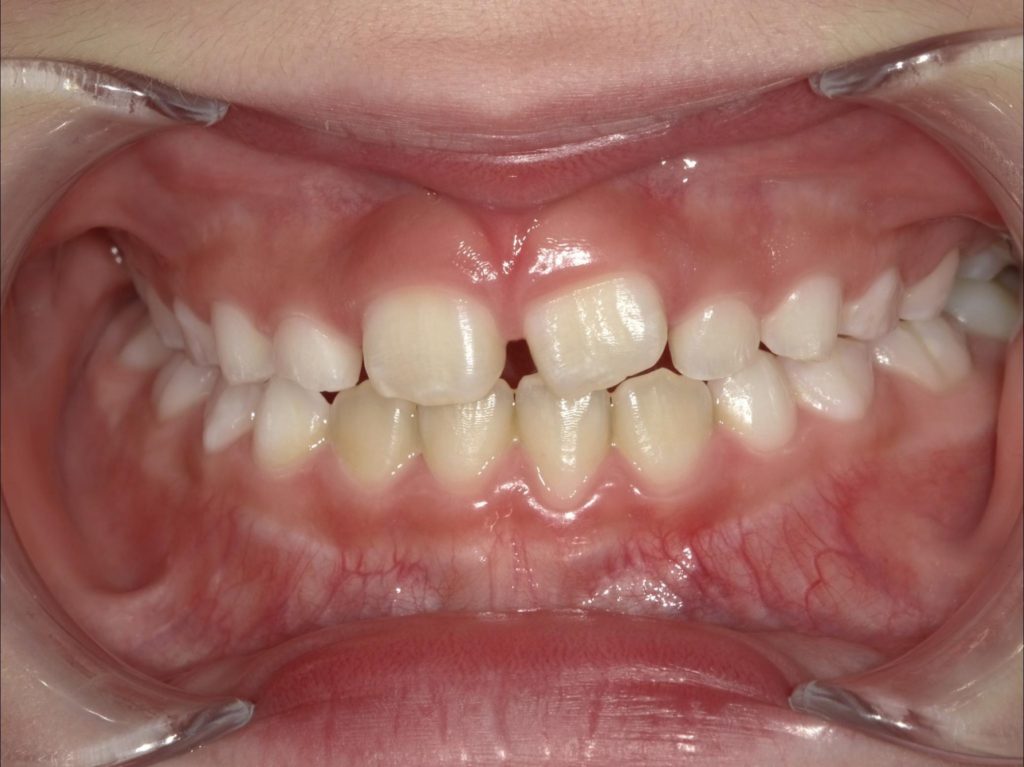

🦷プレオルソ開始から2週間後…✨

プレオルソを毎日正しく装着し、

あわせてお口の使い方のトレーニングを行ったところ…

👉 内側に噛み込んでいた左上の歯が外側へ誘導され、クロスバイトが改善✨

成長期ならではの、

短期間での変化 が確認できました😊🌱

👇

📸【After(2週間後)】